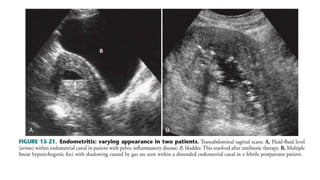

• Sonographically

• the endometrium may appear thick and/or irregular, and the cavity

may or may not contain fluid.

• Gas with distal acoustic shadowing may be seen within the

endometrial canal.